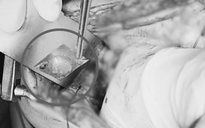

Qua hội chẩn các bác sĩ chuyên khoa tiêu hóa, phối hợp với các bác sĩ ngoại khoa tiến hành mổ nội soi ổ bụng, ghi nhận thủng 8 lỗ ruột non và lấy ra 2 chuỗi viên nam châm, tổng cộng 20 viên. Các viên nam châm được lấy ra đã rỉ sét gây tổn thương ruột nghiêm trọng, các bác sĩ đã khâu vá tất cả các lỗ thủng ruột non.

20 viên nam châm rỉ sét gây thủng ruột non